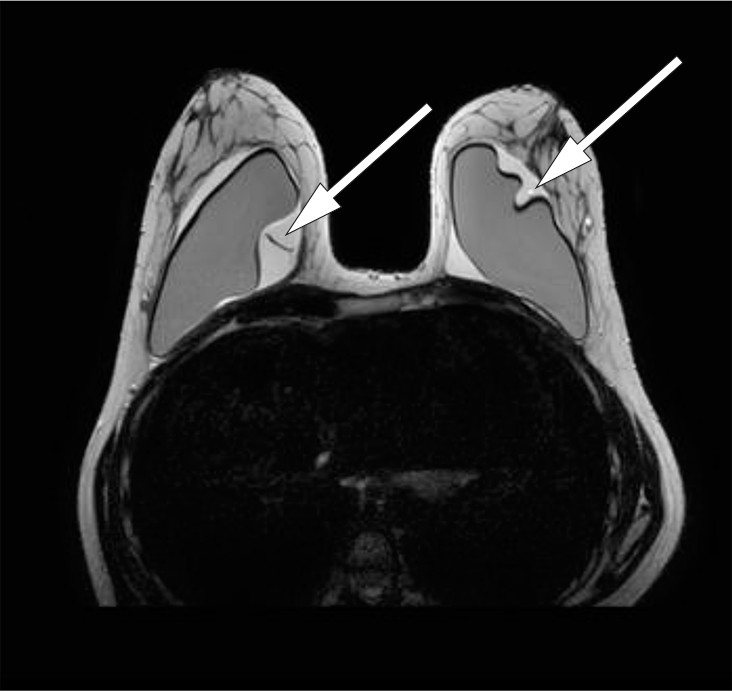

CT-undersøkelse og ultralyd mammae var begge beskrevet som negative med tanke på proteseruptur. Litteraturen beskriver at MR-undersøkelse er foretrukket modalitet, mer sensitiv og spesifikk enn ultralyd- og CT-undersøkelse for å påvise ruptur (1).

MR mammae ga mistanke om proteseruptur, og man så tegn til silikon i aksillære lymfeknuter bilateralt. Mediastinale lymfeknuter kunne ikke vurderes på MR mammae (fig 2, fig 3).